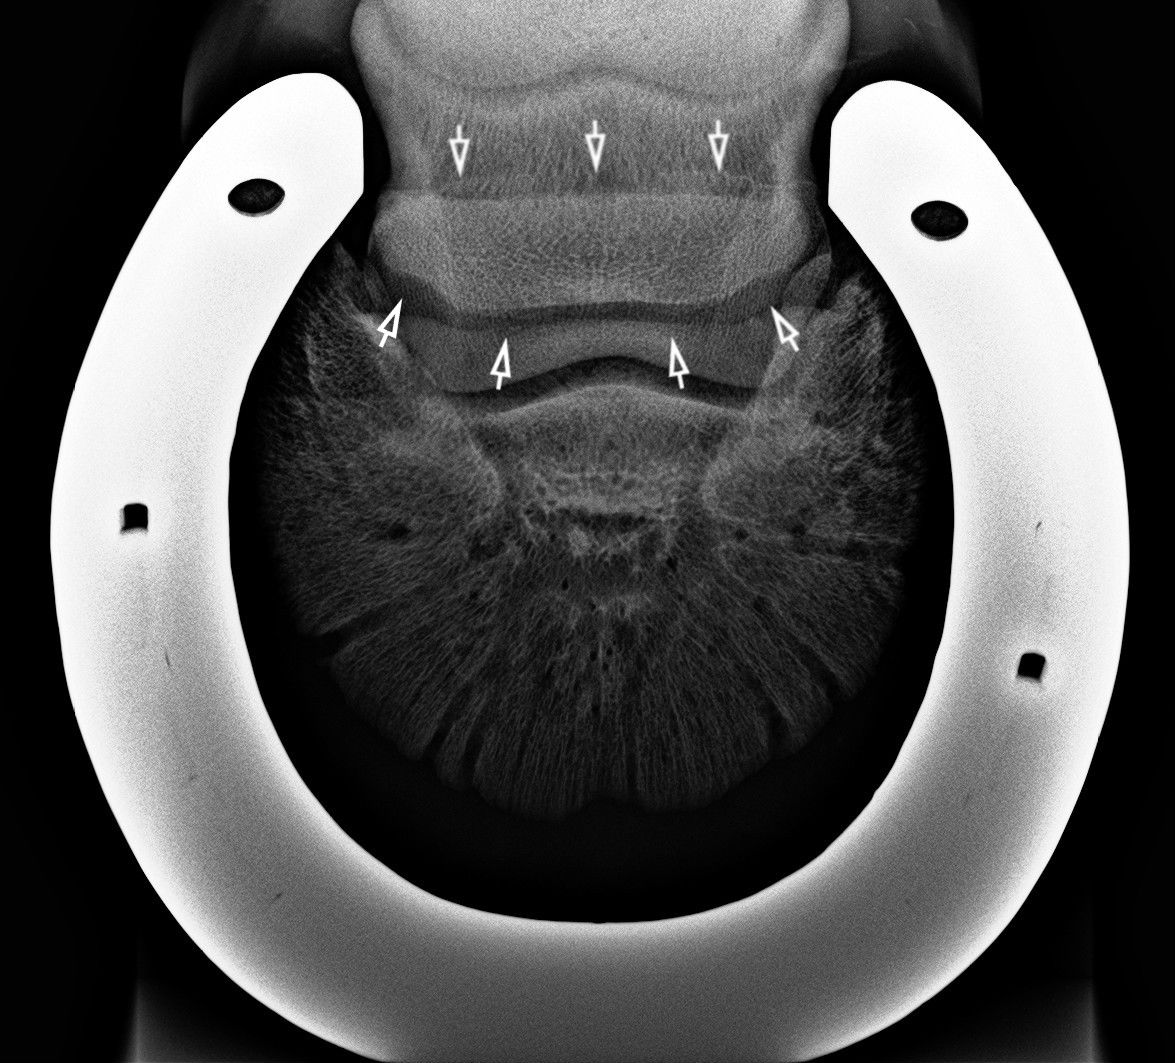

A nyírcsont vizsgálatára szolgáló un. oxspring felvétel. A nyilak a nyírcsontot mutatják.

A másik nyírcsont felvétel, a skyline. Úgy készül, hogy a lovat ráléptetjük a kazettára. A nyilak mutatják a csont helyeződését.